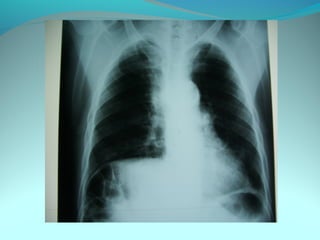

Clarté retroclaviculaire gauche d 3cm de diam

entouré d’une paroi de 1cm d’epaisseur

La limite interne se confend avec le mediastin

Les autre limites sont nette

DIAGNOSTIC

Caverne tuberculeuse gauche